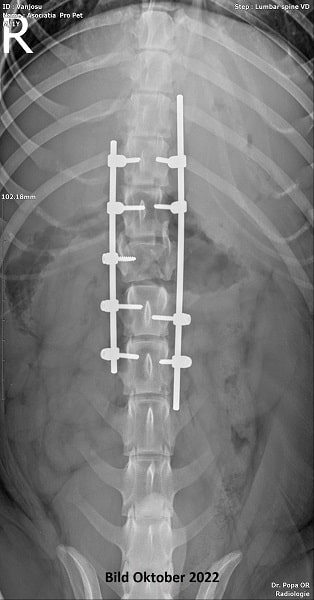

Hinterhand gelähmt, inkontinent, Verletzung am Rücken

Update 04/23: Der liebe Rüde Guiness ist ein sehr menschenbezogener, absolut verschmuster lieber Junge, der leider eine gelähmte Hinterhand hat und dadurch auch inkontinent ist. Zudem hat er eine Verletzung am Rücken. Für den tollen, sehr verträglichen, liebenswerten Buben suchen wir dringend einen Rolli-Platz.

| zur Besonderheit: | Hinterhand gelähmt, inkontinent, Verletzung am Rücken |

| zur Besonderheit: | Hinterhand gelähmt, inkontinent, Verletzung am Rücken |